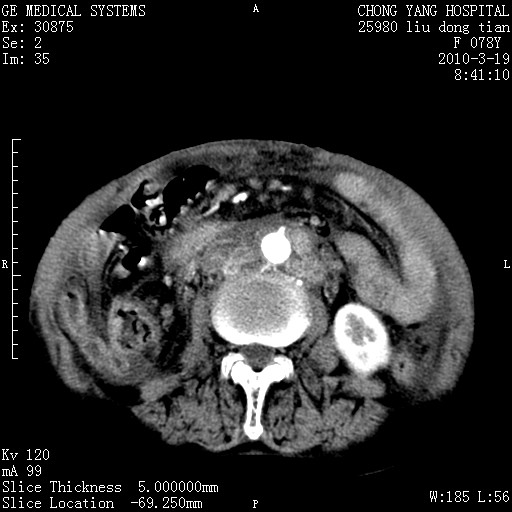

标题: CT25199:F 78Y 腹胀半年 消瘦乏力 [打印本页]

胆囊壁增厚并明显强化,胆囊癌伴多发转移瘤可能性大,淋巴瘤不除外,右肾囊肿,胸腹水.

考虑nhl,肝、脾、腹膜腔及腹膜后多发淋巴结受侵,腹水,右肾囊肿,慢性胆囊炎,右侧少量胸腔积液。

胰头有肿块形成,胰头ca伴肝脾、腹膜腹膜后转移

胆囊有软组织影有强化,支持胆囊癌,肝脾、腹膜后淋巴结转移。

nhl的淋巴结多围绕主动脉,而且主动脉会移位,所以不考虑nhl。

分开来讲:肝左叶、尾叶病灶有不均强化像肝癌;

脾脏病灶无强化,像多发囊肿或淋巴管瘤,不除外淋巴瘤(低强化);

胆囊增生性病变:胆囊癌,腺肌增生症,慢性胆囊炎;

肝门、胰腺头、腹膜后多个团块: 淋巴瘤,转移;

一元论最好了 淋巴瘤所致改变; 胆囊癌转移不像,胆囊周围肝组织清晰,肝癌淋巴结转移?三元论都不止。

脾脏病灶像车轮 莲花,第一感觉还像包虫呢。真想全切出来一个个做病检。

胰头ca伴肝脾、腹膜腹膜后转移!

最后报的胰头癌多发转移,脾脏单独考虑囊肿或淋巴管瘤。